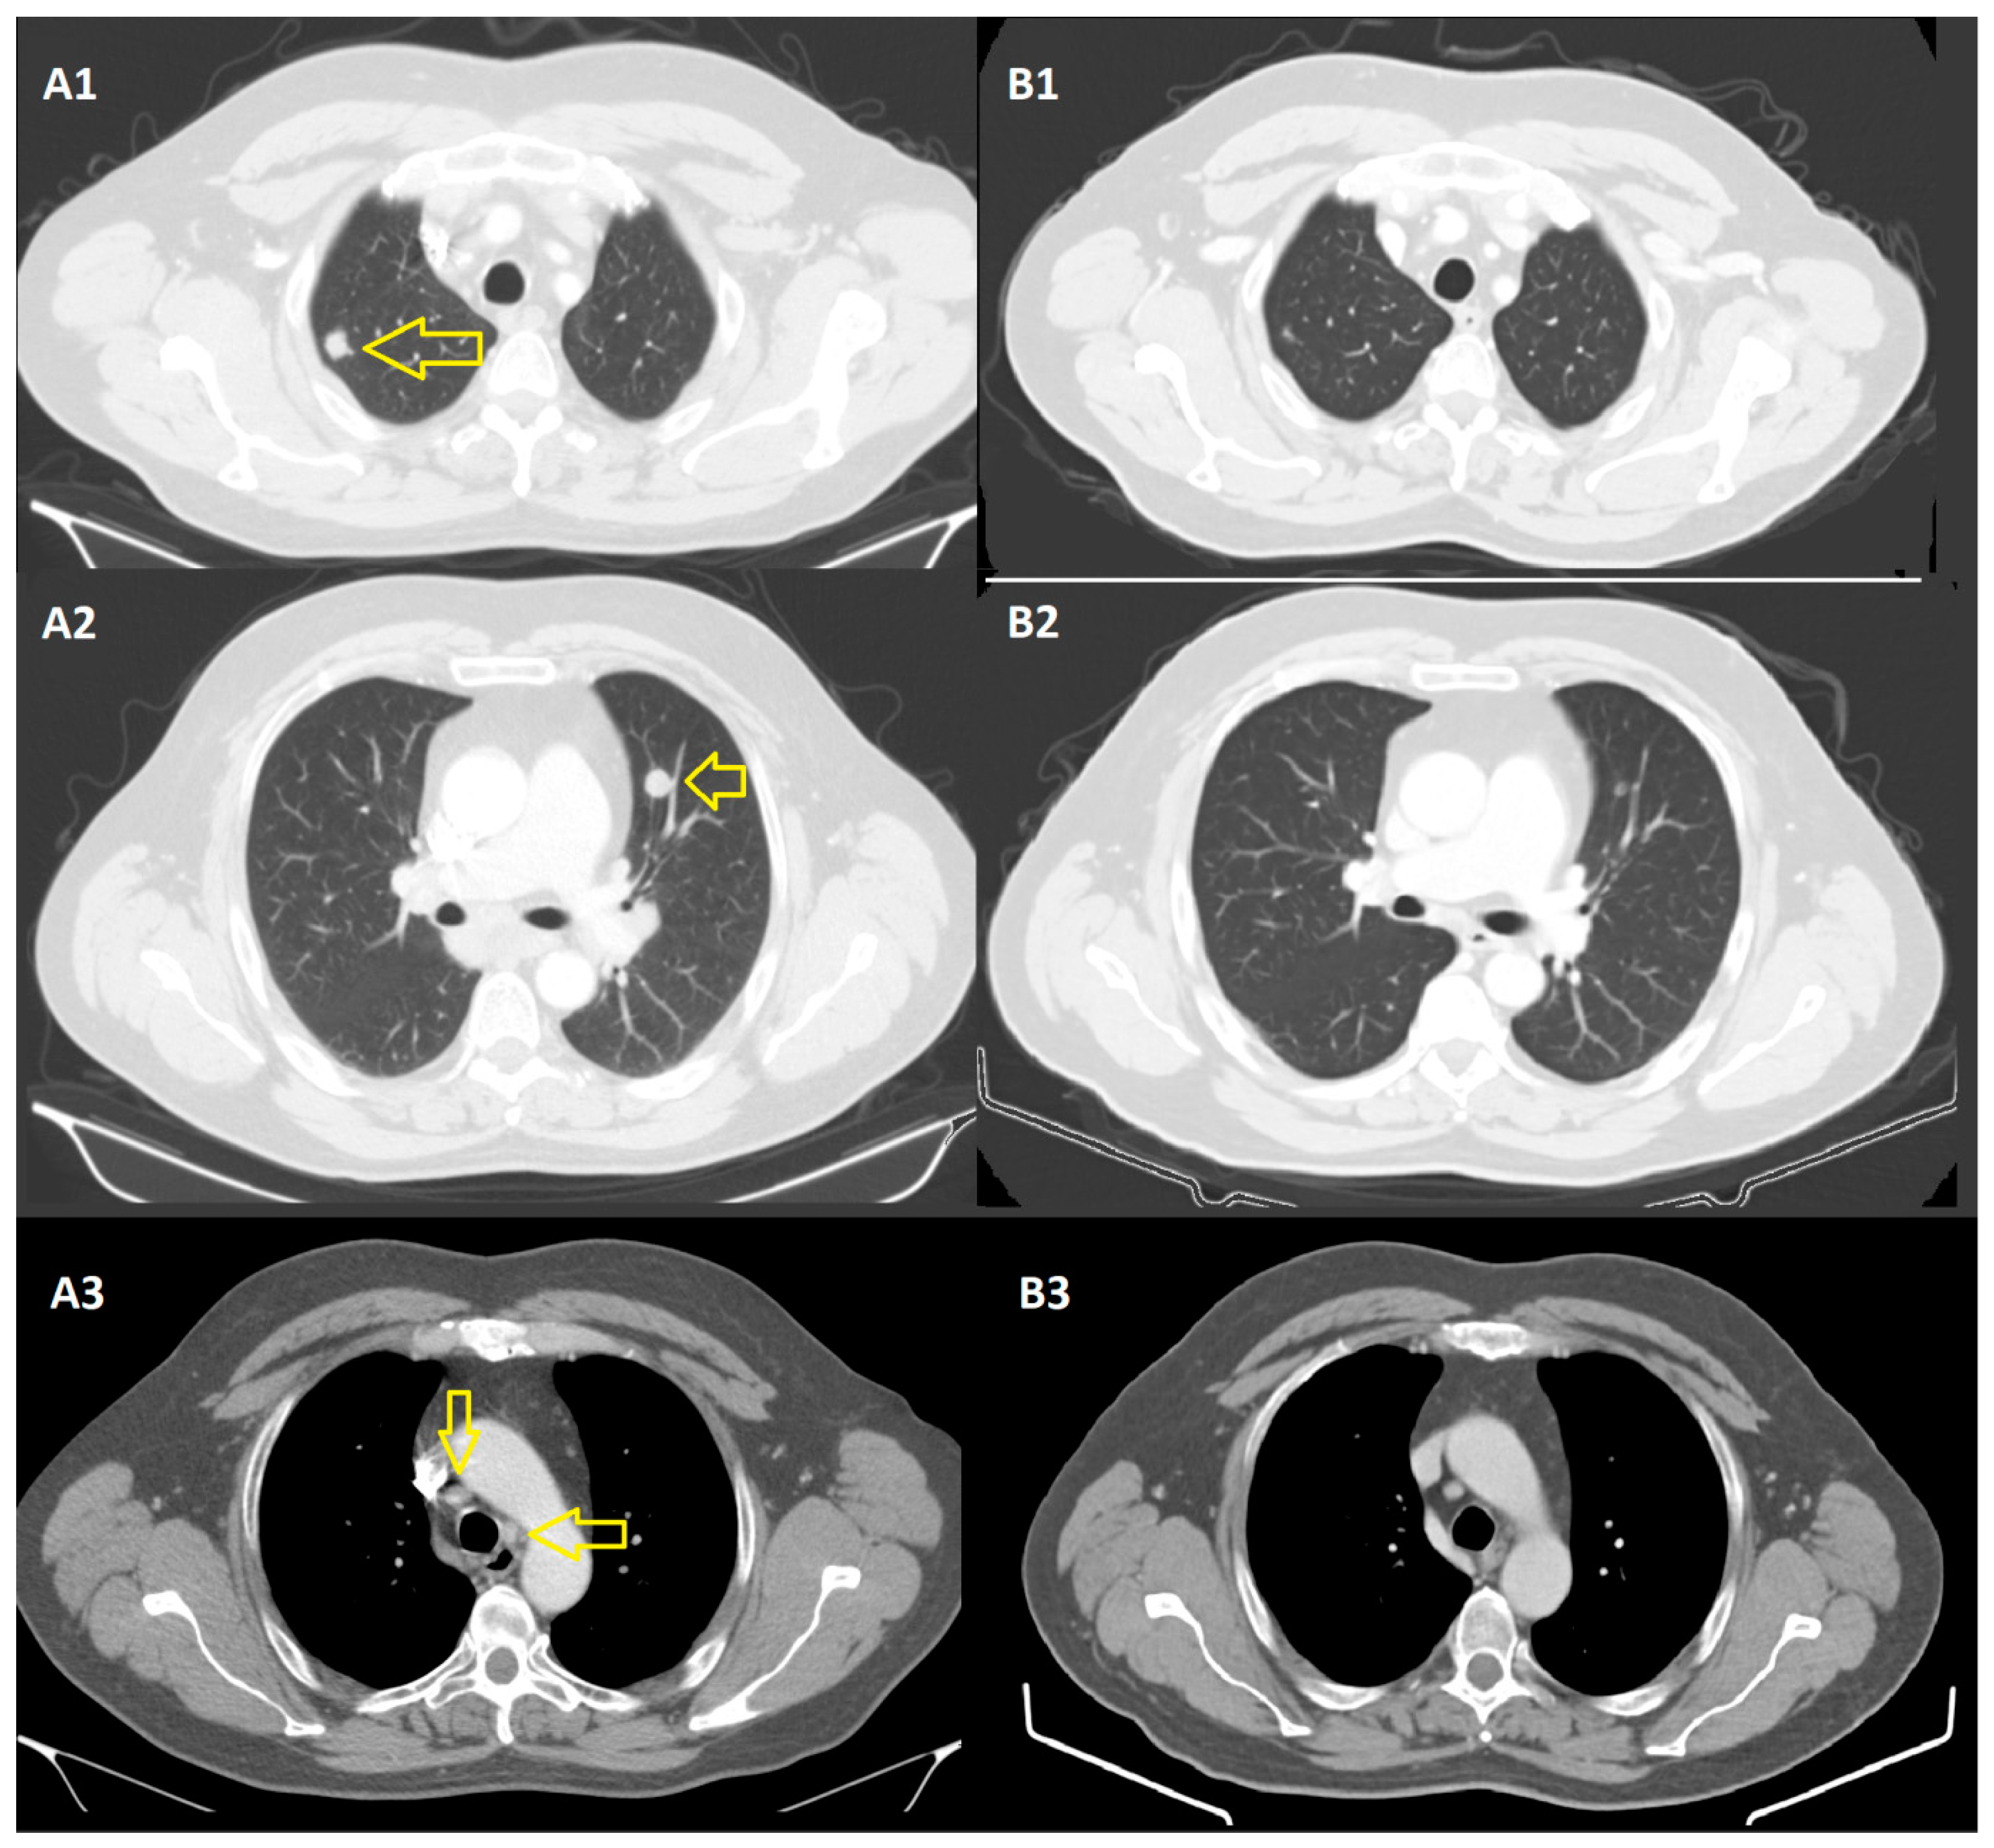

2.2. At the Thoracic Level